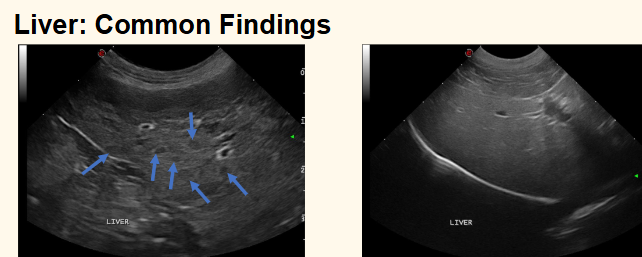

what are these 2 common findings in the liver [during ultrasound]?

-nodular hyperplasia

-diffusely hyperechoic parenchyma